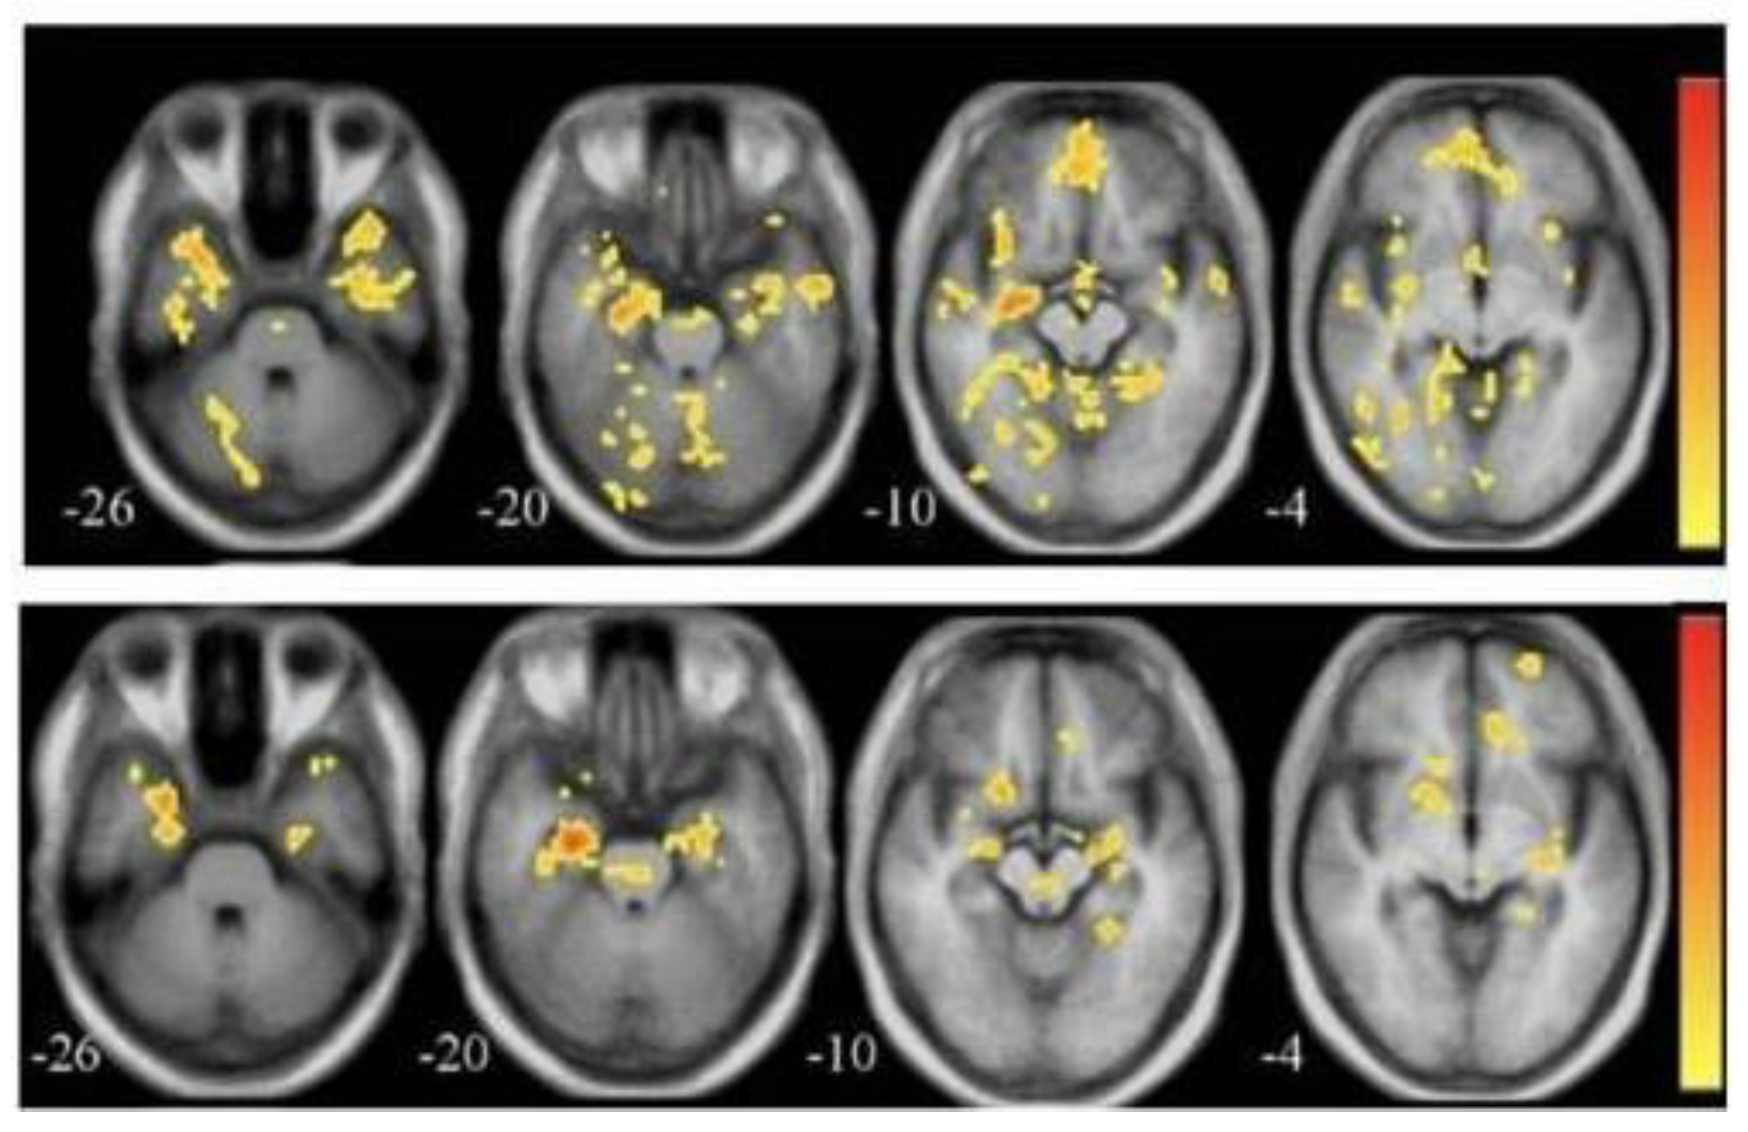

3.2. Functional Magnetic Resonance Imaging (fMRI)